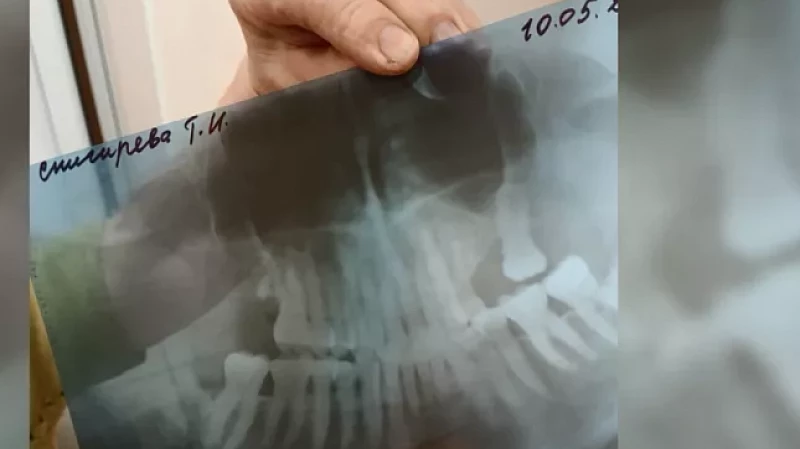

Стоматологи сломали челюсть 85-летней пациентке

Пытались вырвать зуб мудрости, но в итоге сломали челюсть. На Урале 85-летнюю пенсионерку после приёма у стоматолога увезли в госпиталь ветеранов войн, где она попала на хирургический стол. Перелом челюсти оказался со смещением.